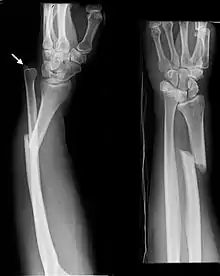

Monteggia Fracture (type of ulna fracture) | |

- Monteggia fracture - a fracture of the near to elbow end of the ulna with the dislocation of the head of the radius at the elbow joint.[2]

- Monteggia Fracture (fracture of proximal ulna)